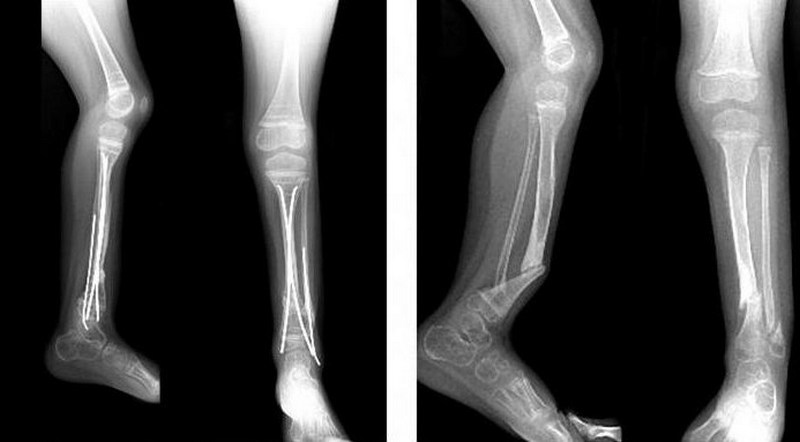

Основной метод подтверждения наличия ложного сустава – прицельная рентгенография, выполняемая минимум в двух проекциях. При необходимости, помимо прямой и боковой проекции, используют добавочные косые, позволяющие лучше детализировать кость. На рентгенограмме не видно признаков костной мозоли, фрагменты кости сглажены и закруглены, а на конце костного отломка появляется плотная замыкательная пластинка.

При атрофическом псевдосуставе концы костных фрагментов сужены, а при гипертрофическом – расширены, что отражает нарушение регенерации кости.

Постоянный остеосинтез

При наложении металлических деталей (пластин или стержней) непосредственно на части кости, говорят об устойчивом, или постоянном остеосинтезе. Подобные конструкции устанавливаются под общим наркозом и требуют своего удаления после полного восстановления целостности кости.